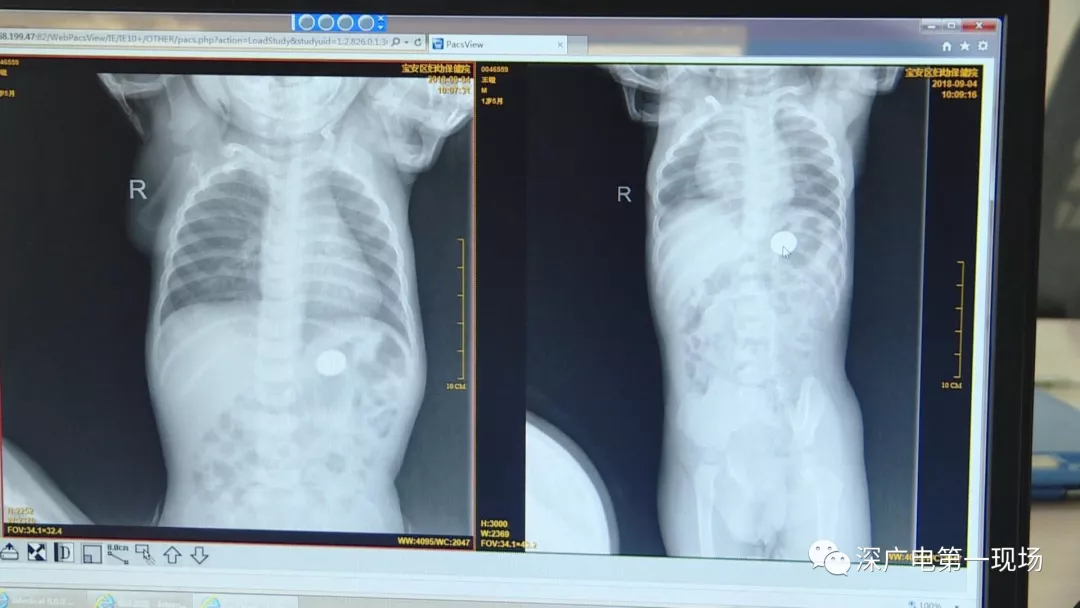

9月4號(hào),一名1歲零5個(gè)月的男嬰因在家中摔傷,被父母送到了寶安區(qū)婦幼保健院,醫(yī)生診斷為左側(cè)尺橈骨骨折。在進(jìn)行全麻手術(shù)之前,院方例行對(duì)嬰兒進(jìn)行了周身檢查。手術(shù)前,兒外科醫(yī)生趙冠聰在查看患者的胸片時(shí),發(fā)現(xiàn)這名嬰兒的胃部有一枚硬幣大小的暗影。

胃部取出一角硬幣

已吞咽半月之久

經(jīng)過兩個(gè)小時(shí)的時(shí)間,兒科醫(yī)生郭景濤為患兒取出了藏在胃底的一角錢硬幣。目前,患兒已經(jīng)痊愈出院。